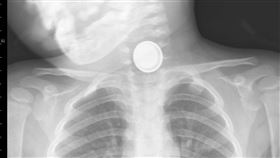

18個月嬰兒吞「鈕扣電池」 媽1句話救命

美國德州一名幼童深夜突然尖叫,父母帶他去醫院,醫生誤...

2025/07/06 12:23